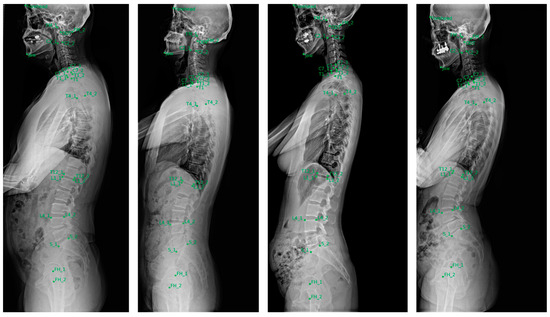

| Name | Description |

|---|---|

| FH_1 | Center of the Femur head |

| FH_2 | Center of the Femur head |

| S_1 | Anterior point of the upper endplate of the sacrum |

| S_2 | Posterior point of the upper endplate of the sacrum |

| L1_1 | Anterior point of the upper endplate of the L1 vertebra |

| L1_2 | Posterior point of the upper endplate of the L1 vertebra |

| L4_1 | Anterior point of the upper endplate of the L4 vertebra |

| L4_2 | Posterior point of the upper endplate of the L4 vertebra |

| T4_1 | Anterior point of the upper endplate of the T4 vertebra |

| T4_2 | Posterior point of the upper endplate of the T4 vertebra |

| T12_1 | Anterior point of the lower endplate of the T12 vertebra |

| T12_2 | Posterior point of the lower endplate of the T12 vertebra |

| T1 | Center of the T1 vertebral body |

| Forehead | Forehead |

| FM_1 | Anterior point of the foramen magnum |

| FM_2 | Posterior point of the foramen magnum |

| ODT | Odontoid |

| Jaw | Jaw |

| C2_1 | Anterior point of the lower endplate of the C2 vertebra |

| C2_2 | Posterior point of the lower endplate of the C2 vertebra |

| C7 | Center of the C7 vertebral body |

| C7_1 | Anterior point of the lower endplate of the C7 vertebra |

| C7_2 | Posterior point of the lower endplate of the C7 vertebra |

| C7_3 | Posterior point of the upper endplate of the C7 vertebra |

| T1_1 | Anterior point of the upper endplate of the T1 vertebra |

| T1_2 | Posterior point of the upper endplate of the T1 vertebra |